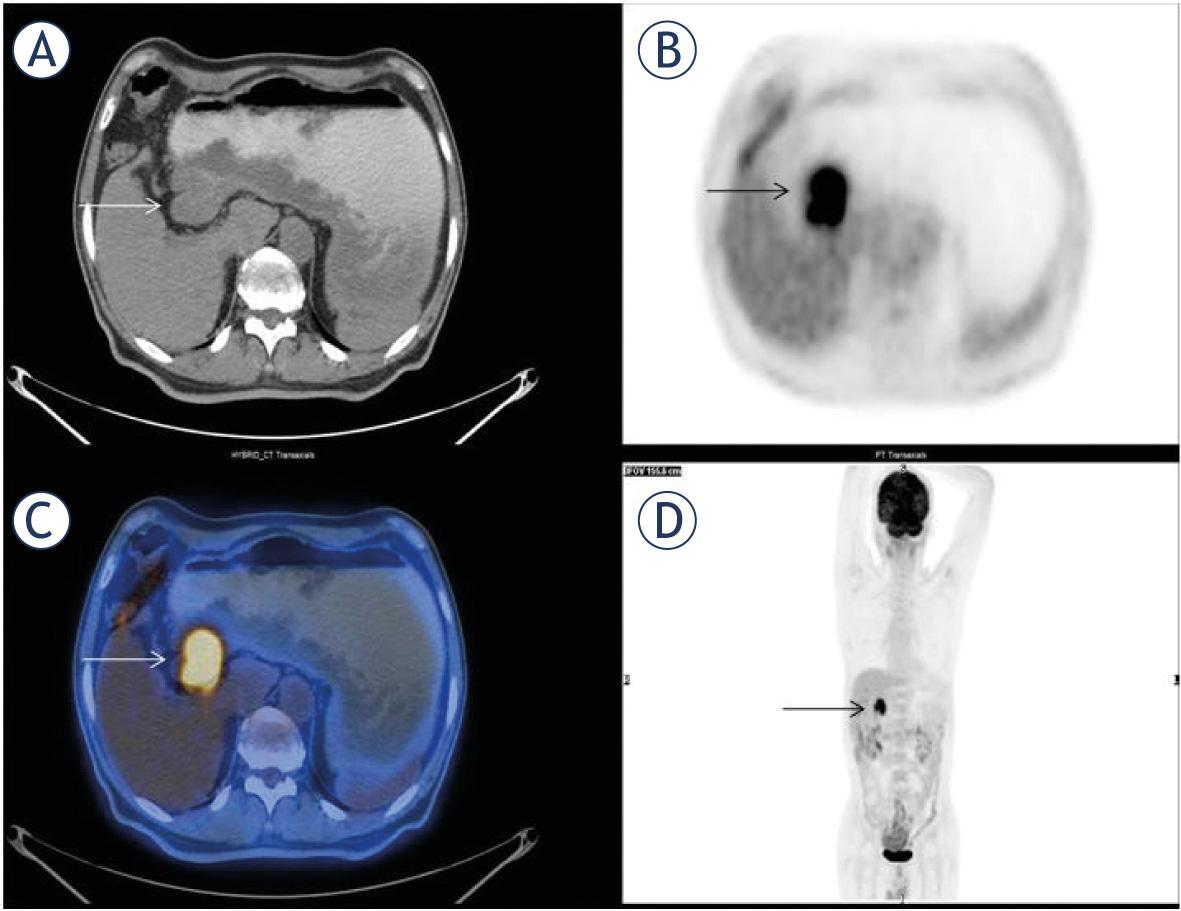

| 1 | 52 | M | DLBC | GIS | Colon | - | - | 7.6 | 4.5 | 12.5 | 56.3 | 44 | 44 |

| 2 | 75 | M | DLBC | GIS | Stomach | - | - | 26.9 | 15.2 | 1212 | 18422 | 40 | 40 |

| 3 | 45 | M | DLBC | GIS | Pancreas | + | + | 20 | 13.1 | 113 | 1483 | 10 | 18 |

| 4 | 65 | M | DLBC | GIS | Jejunum | - | - | 10 | 4.5 | 7 | 31.3 | 67 | 67 |

| 5 | 52 | F | DLBC | GIS | Colon | + | - | 8.6 | 5.8 | 37.3 | 216.4 | 23 | 143 |

| 6 | 72 | F | DLBC | GIS | Stomach | + | + | 27.4 | 18.1 | 29.9 | 541.3 | 8 | 26 |

| 7 | 69 | M | MC | GIS | Stomach | - | + | 10 | 5.2 | 70.1 | 367.6 | 35 | 35 |

| 8 | 64 | F | MALT | GIS | Stomach | - | - | 5.1 | 2.6 | 57 | 148.2 | 63 | 63 |

| 9 | 52 | F | DLBC | GIS | Rectum | + | - | 14.8 | 7.1 | 13.7 | 97.7 | 4 | 39 |

| 10 | 82 | M | DLBC | GIS | Stomach | - | + | 15 | 8.8 | 90.1 | 792.8 | 48 | 48 |

| 11 | 50 | M | DLBC | GIS | Ileum | - | - | 6.1 | 4.4 | 35.2 | 154.8 | 27 | 27 |

| 12 | 25 | M | MALT | GIS | Duodenum | - | - | 6.6 | 4.1 | 30.8 | 126.3 | 122 | 122 |

| 13 | 47 | M | DLBC | GIS | Stomach | - | - | 9.9 | 5.7 | 96 | 547.2 | 111 | 111 |

| 14 | 65 | F | MALT | GIS | Stomach | - | - | 10.1 | 6 | 135.2 | 811.2 | 88 | 88 |

| 15 | 62 | M | MC | GIS | Jejunum | - | - | 5.2 | 3.1 | 29 | 89.9 | 40 | 40 |

| 16 | 80 | F | DLBC | GIS | Stomach | - | - | 5.2 | 2.85 | 10 | 28.5 | 59 | 59 |

| 17 | 35 | M | DLBC | GIS | Stomach | - | - | 39.9 | 21.1 | 144 | 3037 | 17 | 17 |

| 18 | 87 | M | T cell | GIS | Colon | - | - | 7.2 | 4 | 14.3 | 57.2 | 5 | 5 |

| 19 | 33 | M | MALT | GIS | Stomach | - | - | 3.2 | 2 | 17.9 | 36.5 | 34 | 34 |

| 20 | 57 | M | MALT | GIS | Ileum | - | - | 7.6 | 4 | 18.2 | 72.8 | 61 | 61 |

| 21 | 61 | F | DLBC | GIS | Stomach | - | + | 20.1 | 11.15 | 32.1 | 358.2 | 70 | 70 |

| 22 | 56 | M | DLBC | GIS | Stomach | - | + | 15.1 | 8.3 | 50.5 | 419.1 | 123 | 123 |

| 23 | 49 | M | MALT | GIS | Stomach | - | - | 3.45 | 2.8 | 8.5 | 23.75 | 57 | 57 |

| 24 | 77 | M | MALT | GIS | Stomach | - | - | 2.9 | 2.7 | 7.9 | 21.25 | 160 | 160 |

| 25 | 21 | M | Burkitt | GIS | Colon | + | - | 10.6 | 5.2 | 468 | 2423 | 7 | 32 |